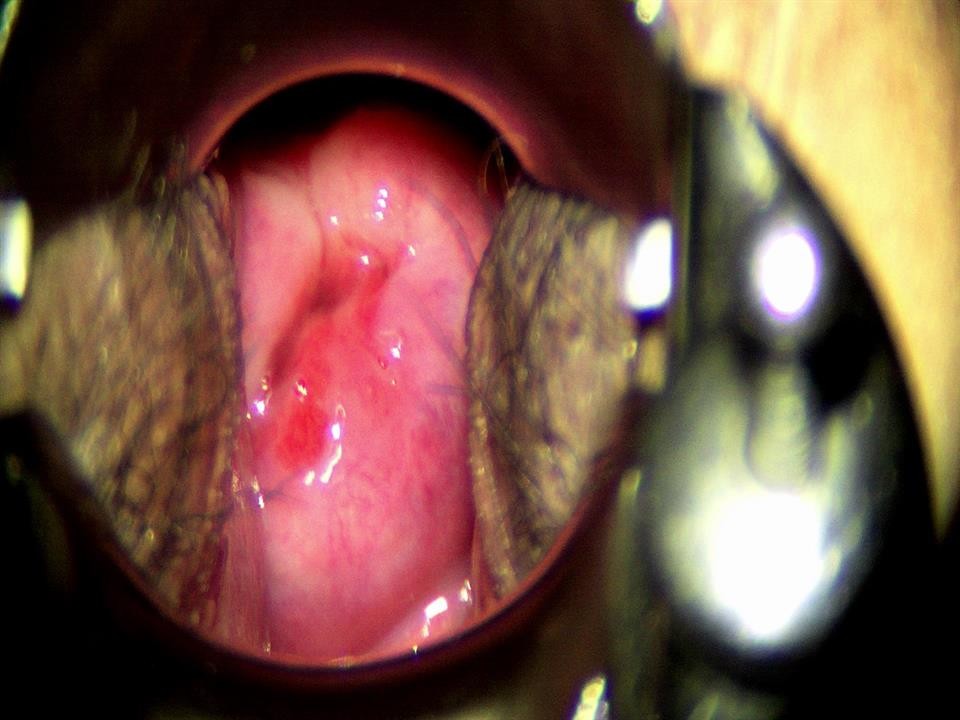

Một tháng sau, kết quả tái khám cho thấy cổ tử cung hồng hào, trơn láng, không còn vết trắng. Bệnh nhân hồi phục tốt, không biến chứng và tiếp tục được theo dõi định kỳ theo hướng dẫn của bác sĩ.